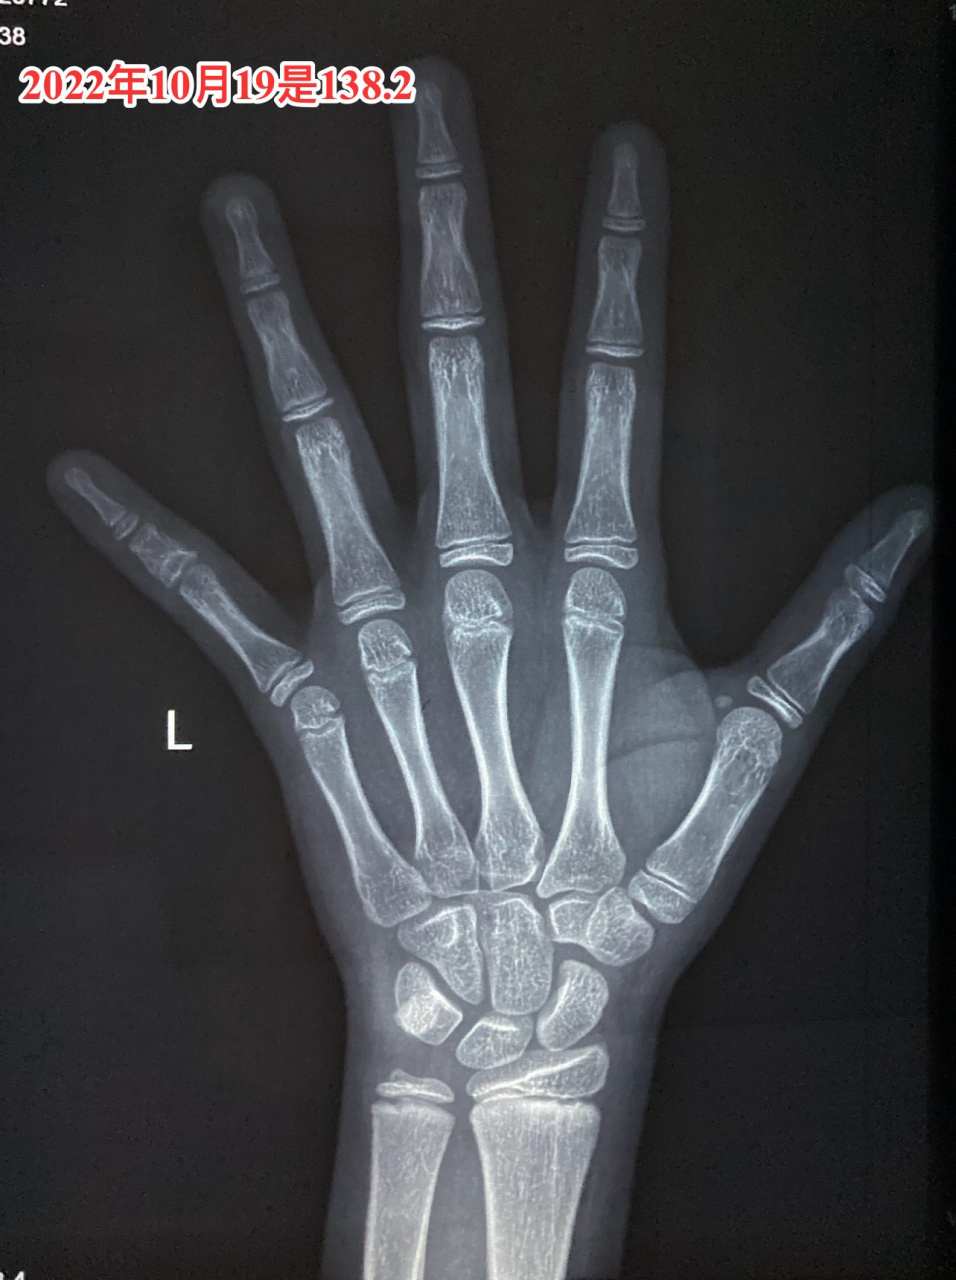

差点又被骗了,籽骨出现不一定是11岁骨龄 差点又被骗了,籽骨出现不

的,十三岁半应该还是不够,尺骨骨骺稍显稚嫩,第一掌指关节区籽骨出现

孩子想长高,骨龄片怎么看,看哪里 很多集美问我籽骨看哪?怎么看?